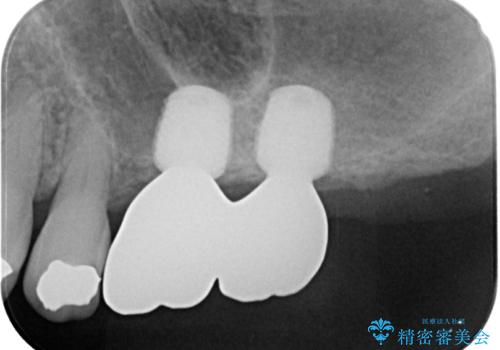

レントゲンから分かるとおり、インプラント埋入に必要な骨の高さが著しく不足している状態でした。

しかしながら、ここ数年で流通してきたデンサーバーというドリルと、エキストラワイドショートインプラントの併用により、骨補填材による上顎洞底の挙上なしに埋入が行えるようになりました。

元々の骨量が少なく、通常よりは待機期間が長くなりますが、数ヶ月程度で補綴治療まで行うことができるため、こちらの手法でインプラント補綴治療を行うこととしました。

インプラントが待機期間に脱落することがありますが、一切のトラブルなく、最短期間で無事に治療を終えることができました。